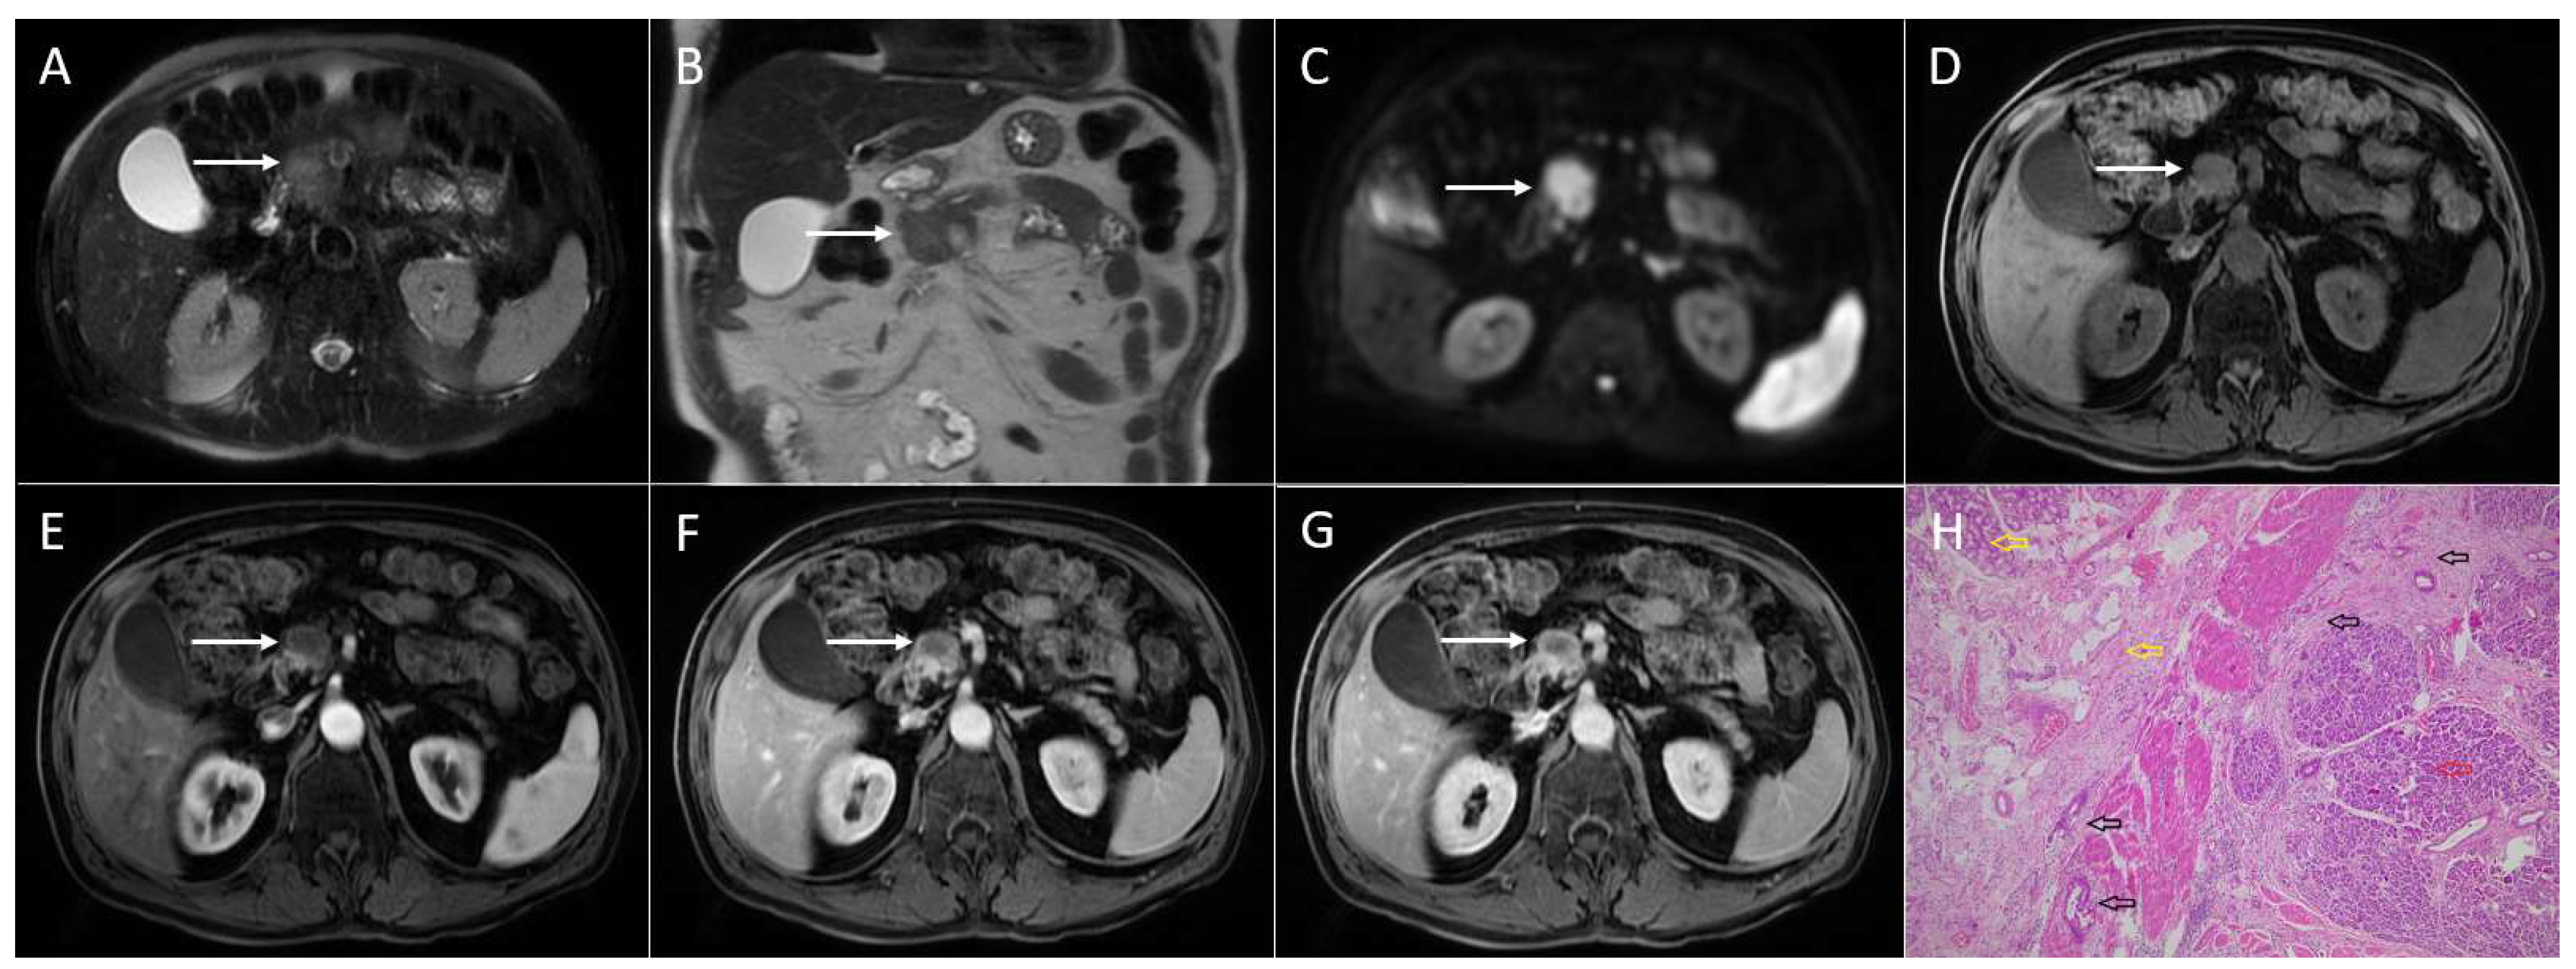

4.3. Walled-Off Necrosis

4.4. Cystic Neuroendocrine Tumors

5. Conclusions